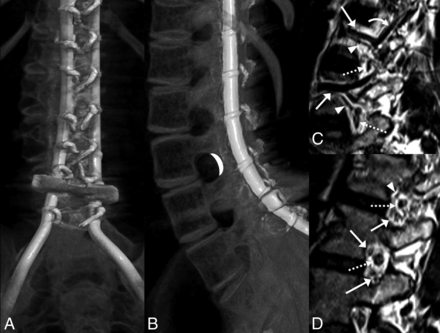

Preprocedural evaluation of lumbar spine radiographs and CT studies revealed extensive spinal fusion hardware and resultant complete osseous interlaminar fusion without any access for classic interlaminar LP (Fig 2). Alternative surgical options discussed with the patients included Ommaya reservoir and lumbar shunt placement (after drilling through the fused laminae). After we discussed the risks and benefits of the different approaches, these 7 patients with SMA decided to proceed with TFLP.

A and B, CT volumetric rendering of a patient with SMA2 demonstrates extensive posterior spinal fusion hardware and complete osseous interlaminar fusion without any access for a classic interlaminar LP. Note the widely patent neural foramina. The white crescent represents the target for TFLP. C and D, Sagittal 3D volumetric T2-weighted images of a healthy person obtained with 3T MR imaging. C, Image obtained slightly lateral to the neural foramen. D, Image obtained at the foramen. Flow voids of the lumbar arteries (arrowheads) and larger caliber lumbar veins (arrows) are seen in the anterior superior aspect of the foramen. A branching ascending lumbar vein is seen coursing toward a higher level neural foramen (curved arrow). More venous structures are seen in the inferior aspect of the foramen (arrows in D). Exiting nerve roots are shown within the center of the foramen (dashed arrows).

When performing TFLP, the proceduralist should be familiar with the anatomic location of the exiting nerve root, the radiculomedullary arteries, and, potentially, the artery of Adamkiewicz. The radiculomedullary branches are in the anterosuperior aspect of the foramen, while the ganglion and exiting nerve root are in the midportion of the foramen (Fig 2). Only smaller branch arteries and veins are found in the posterior aspect of the neural foramen.12 In our method of TFLP, the needle is passed through the posterior portion of the foramen into the spinal canal (Figs 2⇓–4) to minimize the risk of neurovascular injury. Thus, the operator should be proficient with transforaminal procedures as a prerequisite to TFLP.

Prior lumbar imaging is evaluated for each patient to select the safest level and side for the procedure based on the position of the conus medullaris, patency of the neural foramen, and positioning of the adjacent organs. Patients are positioned in the lateral decubitus position. In patients with scoliosis, the convex side is positioned upward. If CT is used for the procedure, an initial low-dose scout CT (80 kVp, 50–80 mAs) is performed with grid placement over the presumed injection side. Even with extensive hardware, the low-dose technique provides adequate visualization of the foramina. The planning CT is evaluated to confirm safety, and the shortest approach to the posterior neural foramen is selected, often necessitating a nearly 90° approach. The overlying skin is prepped, draped, and anesthetized with 1% lidocaine via a 27-ga needle or J-tip. A 22-ga Quincke needle is advanced toward the posterior aspect of the neural foramen under imaging guidance (Figs 3 and 4). It is reported that during LP, orienting the cutting edge of the needle parallel to the longitudinally oriented dural fibers reduces the likelihood of CSF leaks.13,14

Due to scoliosis and altered body wall anatomy, retroperitoneal organs such as the kidney and colon may be located more posteriorly than anticipated, especially as depicted by supine cross-sectional imaging. However, our experience has taught us that the decubitus position often shifts these organs anteriorly, allowing needle trajectories that did not appear feasible on the planning supine imaging (Fig 4).